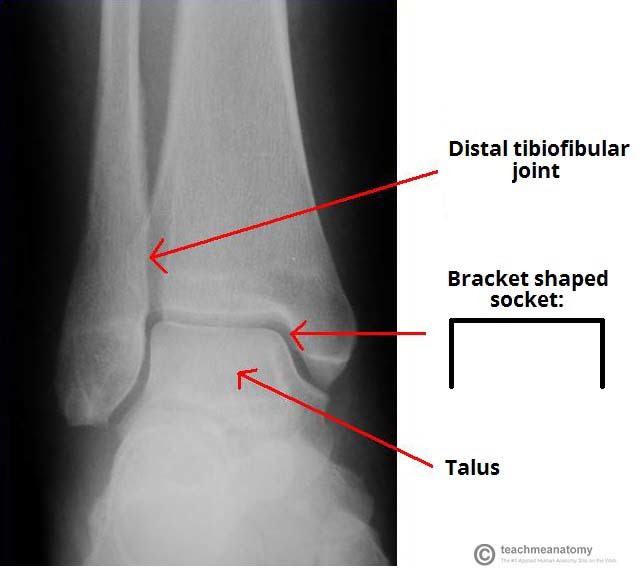

What is the mortise?

The ankle joint and the associated ligaments can be visualised as a ring in the coronal plane.

Identify and describe the borders of this ring